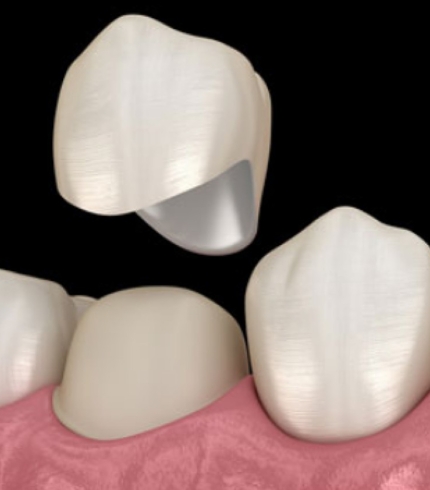

Çene Kisti Operasyonları yapılırken kist uygulanabiliyorsa tek parça halinde alınmaya çalışılır. Büyük ölçekli kistler önce küçültülür daha sonra cerrahi işlemle alınır. Çene kistleri çene kemiğinde ya da diş köklerinde bulanabilir. Eğer kist diş köklerindeyse operasyon sırasında kist ile ilgili diş ağızda bırakıldıysa dişe kanal tedavisi uygulanır ya da operasyon sırasında diş çekildiyse daha sonra ilgili dişe implant tedavisi uygulanır. Operasyon sonrasında bu süreç hem cerrah hem de hasta tarafından dikkat edilmesi bir dönemdir.